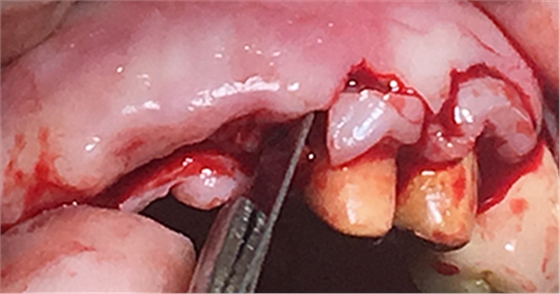

水平切口,鄰牙冠延長(zhǎng)。

擴(kuò)孔,檢查方向。

大家注意這個(gè)動(dòng)作,雖然不翻瓣,但要將唇側(cè)倒凹處骨膜剝離。

植入植體。

將骨粉塞入剝離的骨膜下間隙里既唇側(cè)倒凹處,盡量塞滿。